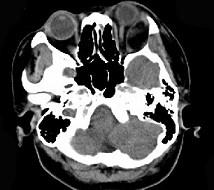

问题 女,52岁,左眼球突出二十余年, T3、T4均正常,影像检查如图所示,应诊断为 ( )

选项 A、血管瘤 B、炎性假瘤 C、脂肪瘤 D、畸胎瘤 E、错构瘤

答案 E